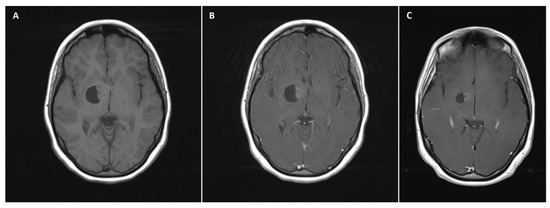

A 21-month-old boy with a left lateral ventricle choroid plexus cyst diagnosed by means of USG in the neonatal period underwent CT and subsequent MRI due to progressive cyst enlargement. Imaging studies revealed a tumor of the choroid plexus within the left collateral triangle (Figure 2A,B). At admission, the patient was neurologically intact, with normal psychomotor development and no signs of raised ICP. Physical examination revealed slight cranial asymmetry, with bulging of the left parietal bone. The patient qualified for surgical tumor removal based on progressive enlargement of the pathologic mass. GTR of the tumor was achieved. In the early postoperative course, a few episodes of vomiting with raised body temperature occurred, but the patient remained neurologically intact. No signs of infection were detected in the blood tests. A postoperative head MRI scan confirmed complete tumor excision (Figure 2C). The patient was discharged home in an asymptomatic clinical state. Pathological examination revealed choroid plexus papilloma (WHO grade 1 tumor). The patient was followed up for 86 months with no radiological signs of tumor recurrence. Concurrently, episodes of sporadic syncope occurred clinically, but due to the lack of direct relation with surgical intervention, they were not considered to be associated with the tumor removal procedure.

Figure 2. A 21-month-old boy with choroid plexus papilloma of the left lateral ventricle. (A) A preoperative axial non-contrast T1 MRI scan with a hypodense mass located within the left occipital horn of the lateral ventricle with cystic components. (B) The preoperative axial postcontrast T1 MRI scan showed homogeneous intraventricular mass enhancement, reflective of choroid plexus papilloma. (C) A postoperative axial postcontrast T1 MRI scan reflecting complete excision of the intraventricular mass, with the remaining cystic component.